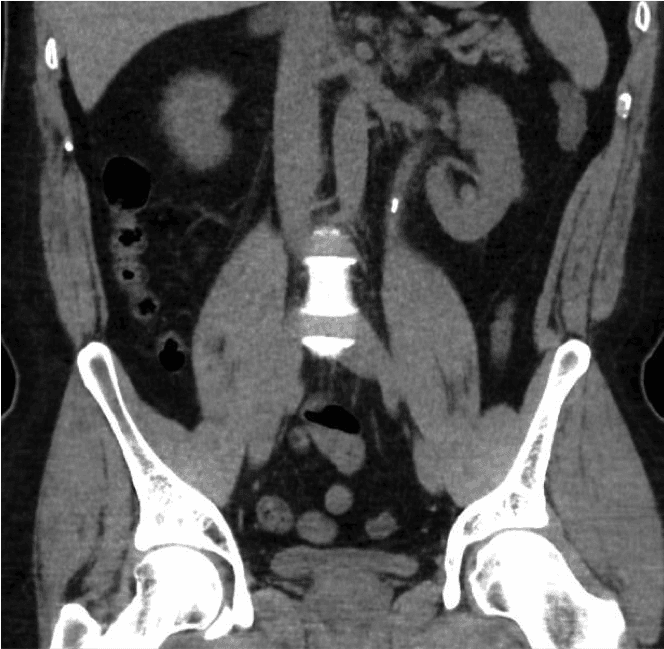

Inicialmente, se realizará una prueba de orina con tira reactiva para detectar sangre y descartar una infección urinaria. Se realizan análisis de sangre para evaluar la función renal y el calcio. La prueba diagnóstica definitiva para cálculos es una tomografía computarizada simple del abdomen (TC del área del riñón, uréter y vejiga o TC KUB). Esta tomografía mostrará el tamaño y la posición de los cálculos, lo que ayudará a planificar el tratamiento.